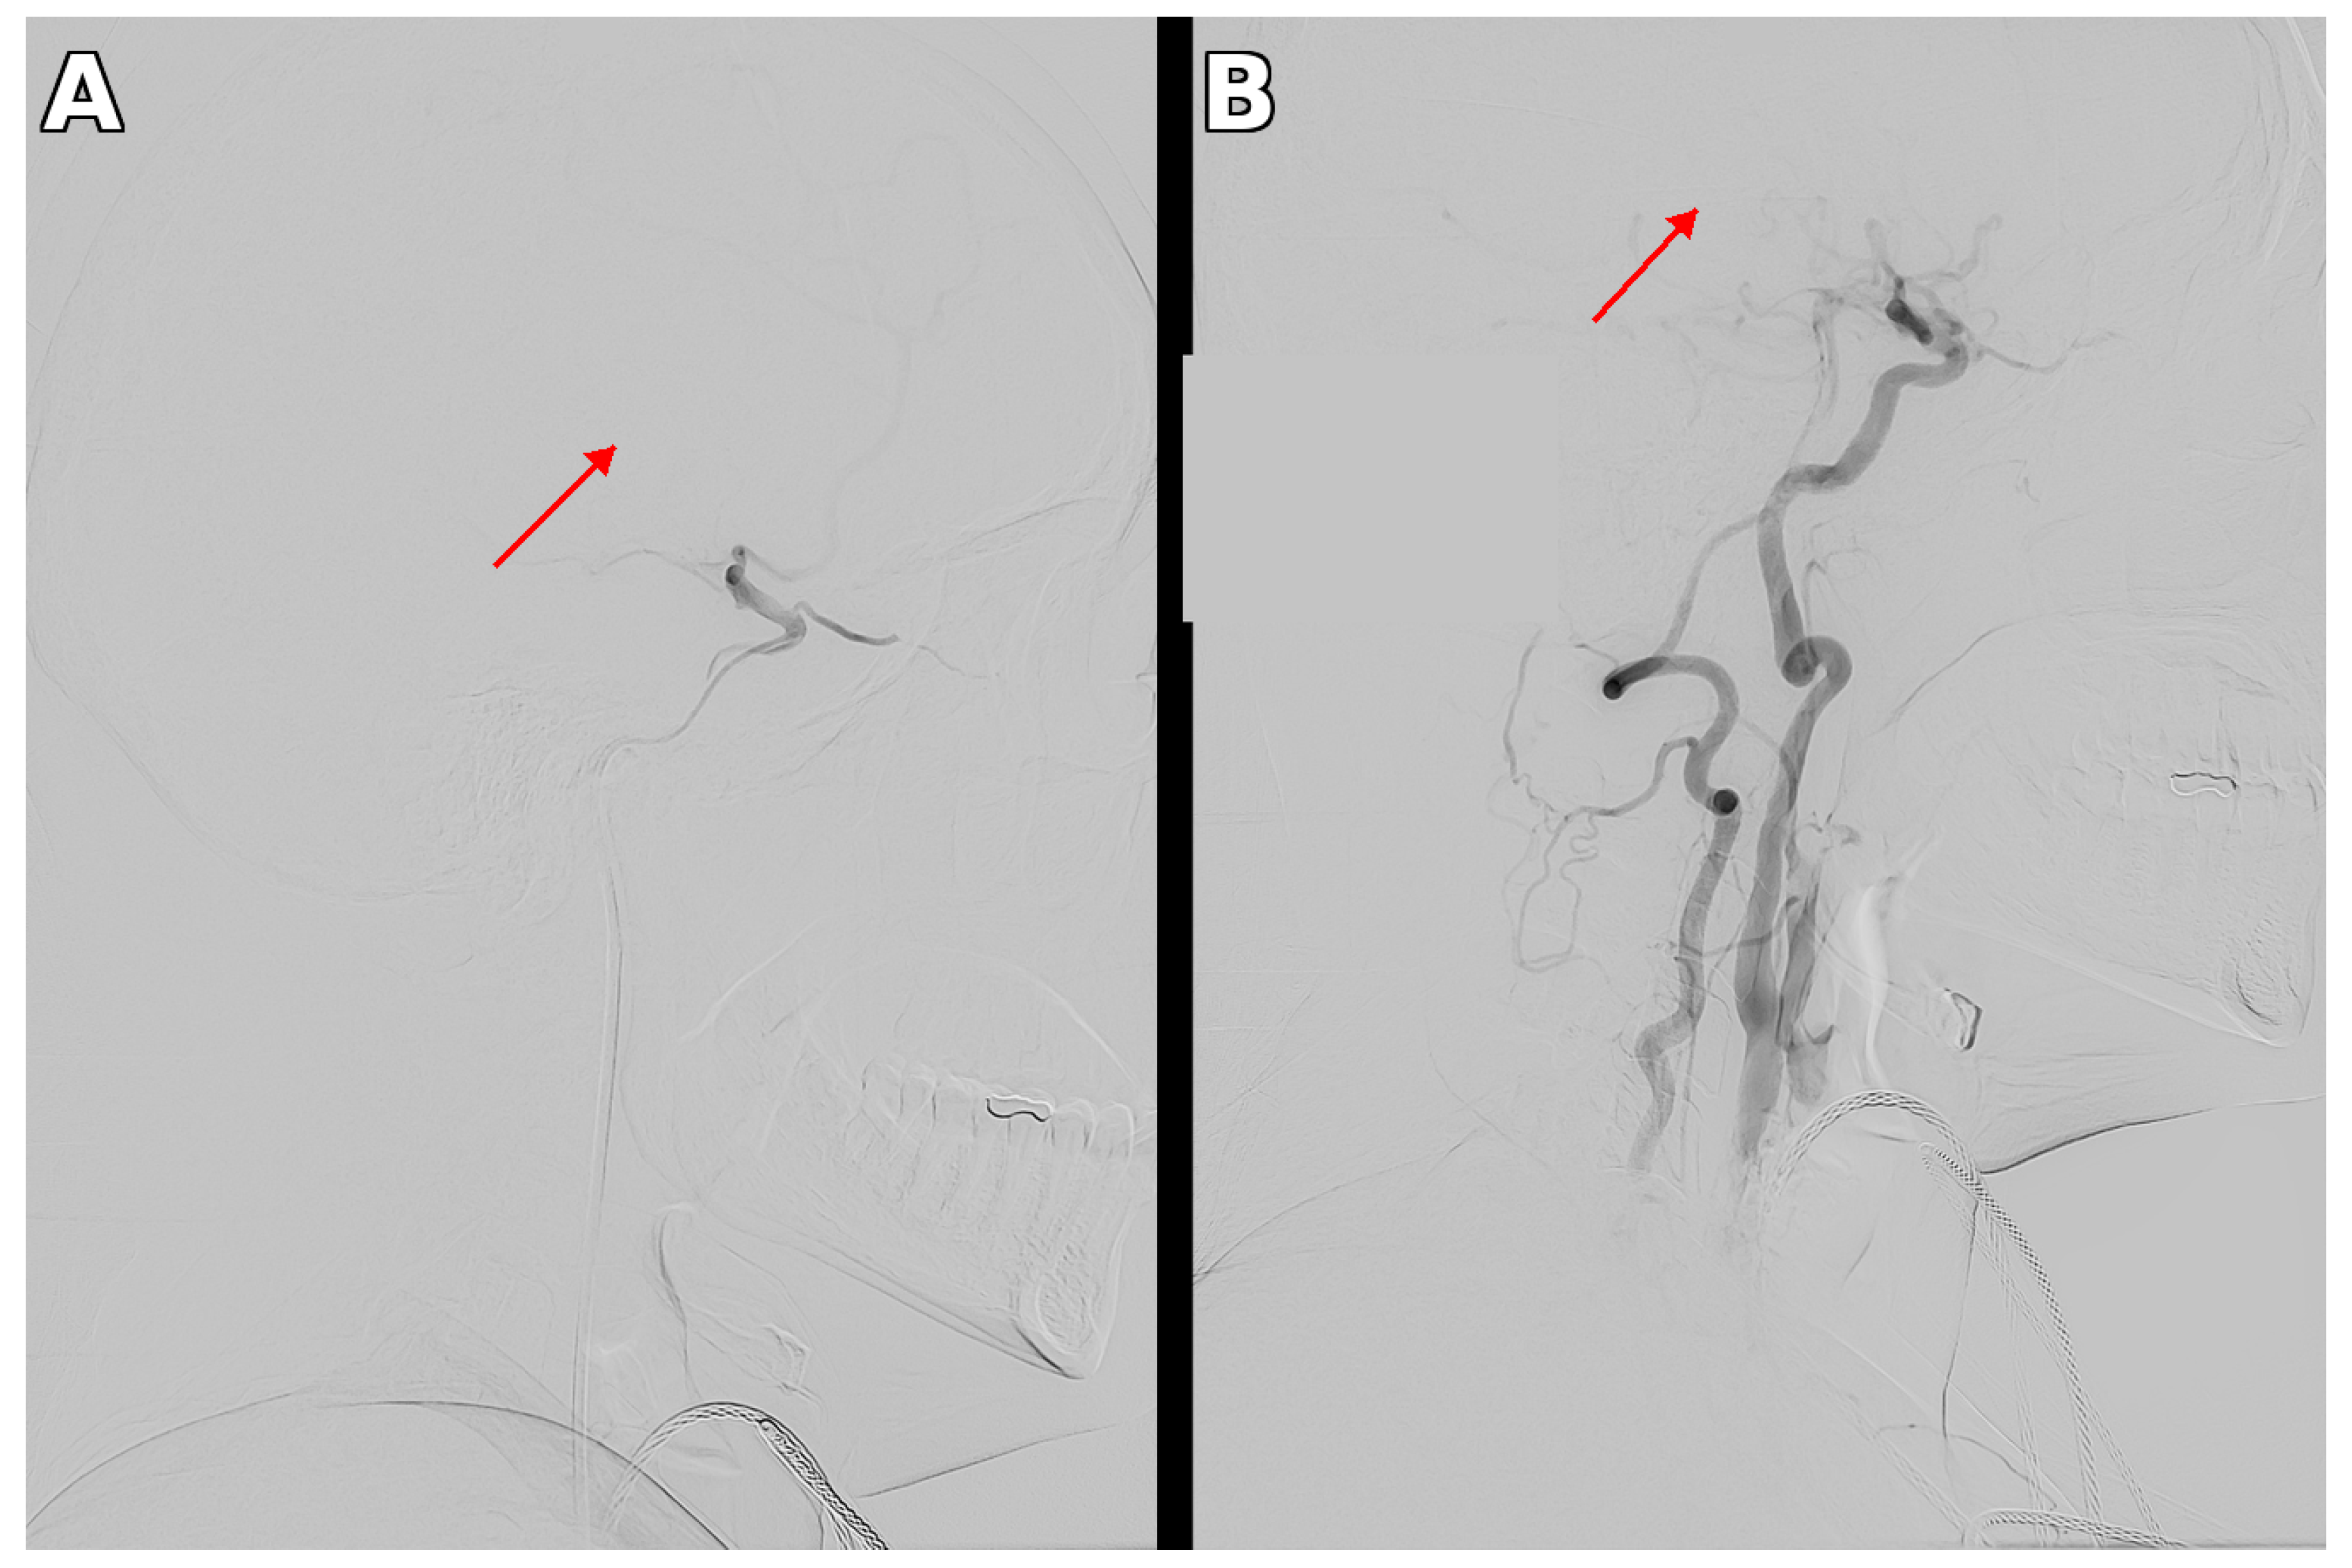

3.1. Therapeutic Intervention